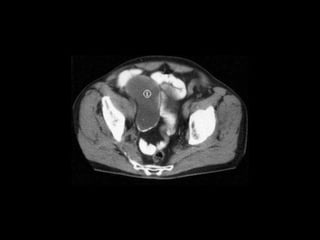

Pseudomyxoma peritonei (PMP) is a rare condition characterized by gelatinous ascites resulting from the rupture of appendiceal mucinous tumors, leading to significant abdominal complications. The incidence is approximately 2 cases per million per year, with a predominance in females, and diagnosis often relies on imaging techniques like ultrasound and CT scans. Effective treatment involves cytoreductive surgery combined with hyperthermic intraperitoneal chemotherapy (HIPEC) to manage disease progression and improve outcomes.